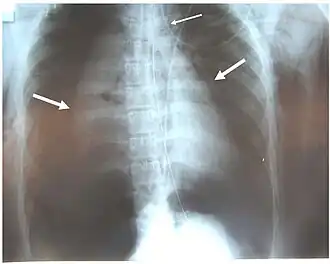

Pneumothoraces of both lungs (large arrows), pneumomediastinum (small arrow) and subcutaneous emphysema in a patient with complete disruption of the right bronchus. Air leak was continual despite suction.[1]

Signs and symptoms vary depending on what part of the tracheobronchial tree is injured and how severely it is damaged.[6] There are no direct signs of TBI, but certain signs suggest the injury and raise a clinician's suspicion that it has occurred.[8] Many of the signs and symptoms are also present in injuries with similar injury mechanisms such as pneumothorax.[9] Dyspnea and respiratory distress are found in 76–100% of people with TBI, and coughing up blood has been found in up to 25%.[10] However, isolated TBI does not usually cause profuse bleeding; if such bleeding is observed it is likely to be due to another injury such as a ruptured large blood vessel.[2] The patient may exhibit dysphonia or have diminished breath sounds, and rapid breathing is common.[3] Coughing may be present,[11] and stridor, an abnormal, high-pitched breath sound indicating obstruction of the upper airway can also occur.[12]

Damage to the airways can cause subcutaneous emphysema (air trapped in the subcutaneous tissue of the skin) in the abdomen, chest, neck, and head.[2] Subcutaneous emphysema, present in up to 85% of people with TBI,[10] is particularly indicative of the injury when it is only in the neck.[13] Air is trapped in the chest cavity outside the lungs (pneumothorax) in about 70% of TBI.[4][10] Especially strong evidence that TBI has occurred is failure of a pneumothorax to resolve even when a chest tube is placed to rid the chest cavity of the air; it shows that air is continually leaking into the chest cavity from the site of the tear.[11] Air can also be trapped in the mediastinum, the center of the chest cavity (pneumomediastinum).[4] If air escapes from a penetrating injury to the neck, a definite diagnosis of TBI can be made.[10] Hamman's sign, a sound of crackling that occurs in time with the heartbeat, may also accompany TBI.[14]